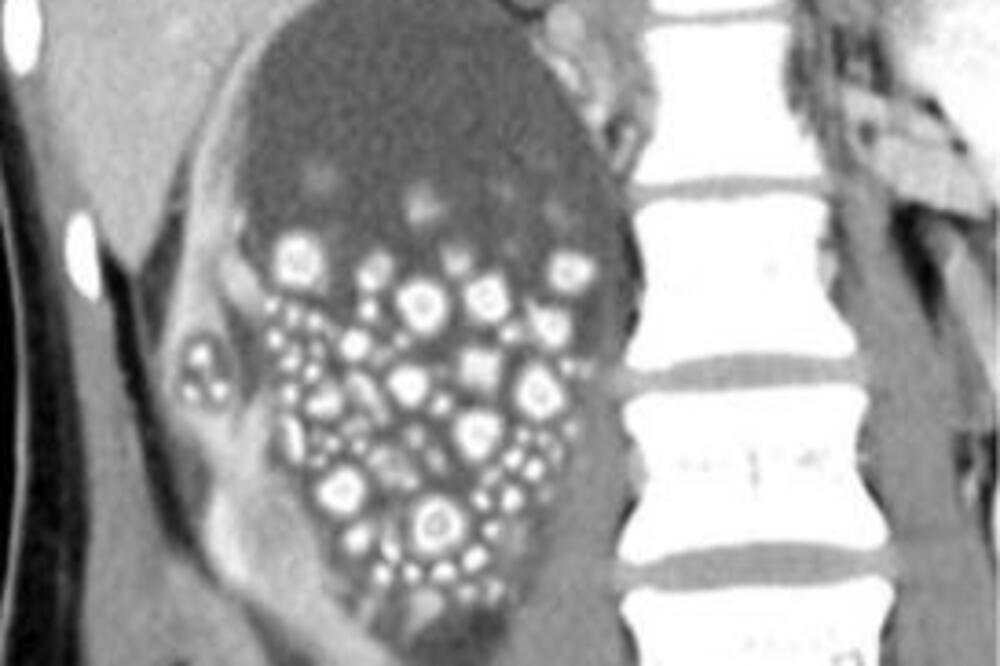

Xiao Yu primljen je u bolnicu Chi Mei na Tajvanu u prosincu 2023. zbog groznice i jake boli u donjem dijelu leđa. Ultrazvuk je otkrio stotine bubrežnih kamenaca u njenom natečenom desnom bubregu, veličine od pet milimetara do dva centimetra.

Yu je priznala da je godinama izbjegavala vodu i umjesto toga pila voćne sokove i alkohol, što je rezultiralo kroničnom dehidracijom i nakupljanjem minerala u bubrezima. Liječnici su je operirali dva sata i navodno izvadili tristotinjak bubrežnih kamenaca.